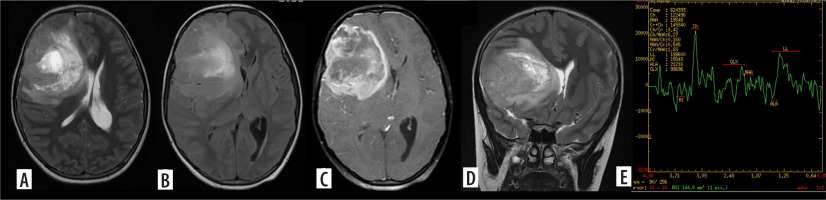

Figure 2

Glioblastoma. Axial T2, T2/FLAIR (A, B) and post contrast images (C) and coronal T2 (D) show a T2 intermediate lesion with intralesional necrosis in the right frontal lobe showing intense ring-like post contrast enhancement. Advanced magnetic resonance imaging evaluation with magnetic resonance spectroscopy shows absolute choline peak elevation with Ch:NAA 6.27 and Ch:Cr 3.42